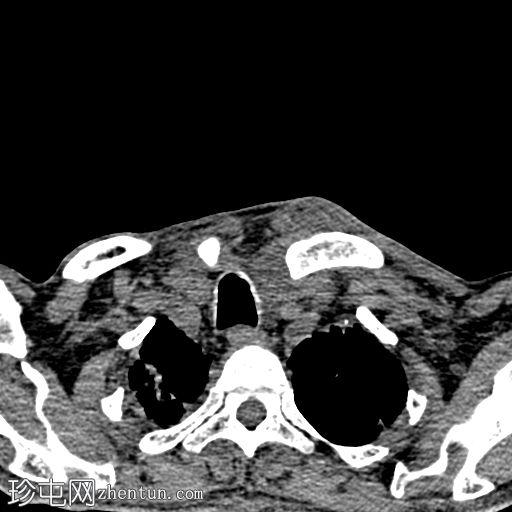

CT

轴位

平扫

轴位增强扫描

动脉期

CT显示胸锁关节周围强化的积液,伴邻近软组织炎症和锁骨内侧骨侵蚀,符合化脓性关节炎和脓肿的

影像

学表现。